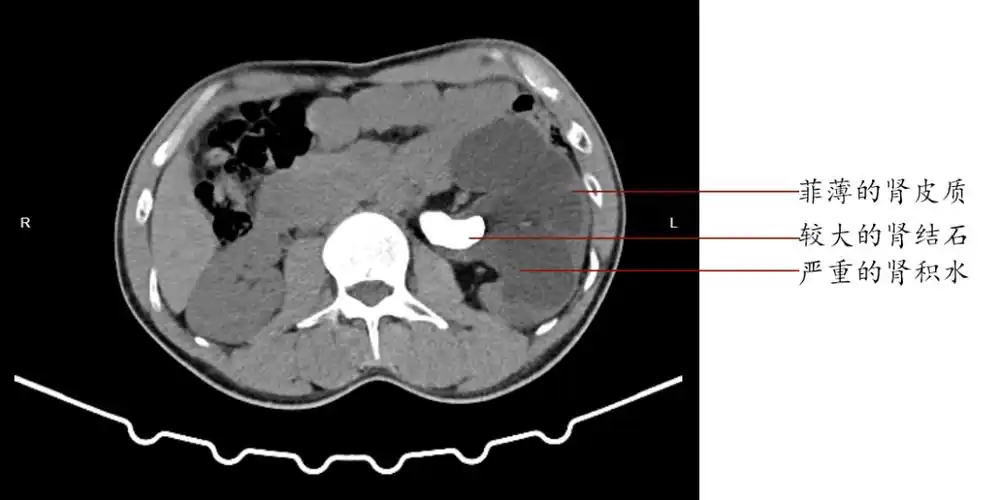

泌尿系统结石之肾结石ct表现

最新进展 > 正文 后进行ct平扫时,除了发现左侧肾盂结石以外,细心的